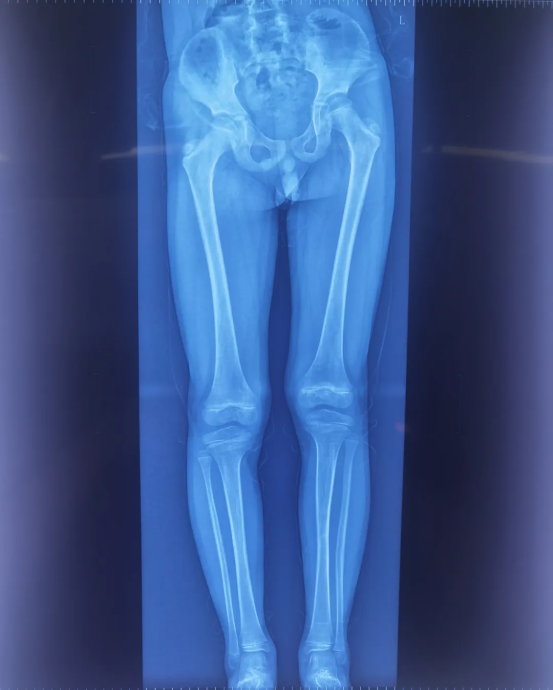

When children and adolescents suffer from gait abnormalities, compensatory spine scoliosis and other issues due to lower limb length discrepancy, epiphysiodesis of the knee (figure-eight plate) emerges as a key option to improve their growth and development. With its professional 3D imaging, Perlove Medical’s 3D C-arm is applied in the entire surgical process. Centered on precise imaging, it overcomes the difficulties in surgical operations and provides reliable imaging support for bone correction in children and adolescents.

Screw placement is a critical step in the surgery. It requires accurate placement in specific epiphyseal regions of the femur and tibia, which not only achieves the growth inhibition effect but also avoids damaging healthy epiphyses, blood vessels, or nerves, imposing demanding exceptional surgical accuracy. When locating the target sites (such as the femur and tibia) , surgeons can clearly identify the position of the epiphyseal plate using Perlove Medical’s 3D C-arm. This helps them define the safe zones for drilling and screw insertion, establish an optimal relative relationship between the screws, epiphyses, and bone axes, and eliminate risks like screw deviation or bone penetration.